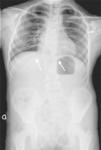

Nuestra paciente inicialmente se diagnostica de SJL dada la presencia de tórax en escudo, T12 en mariposa, fusión vertebral L1-L2-L3, y anomalías costales (fusión de la undécima y duodécima costilla derecha, anomalías morfológicas de segunda y tercera costilla derecha y ausencia de la primera costilla derecha) (fig. 2). Posteriormente, dada la ausencia de útero y porción superior de la vagina se une el diagnóstico de SMRKH. Actualmente la paciente presenta escoliosis no progresiva con curva dorsal derecha de 45°, patrón respiratorio restrictivo moderado y no tiene lesiones cardíacas residuales; mantiene seguimiento multidisciplinar.